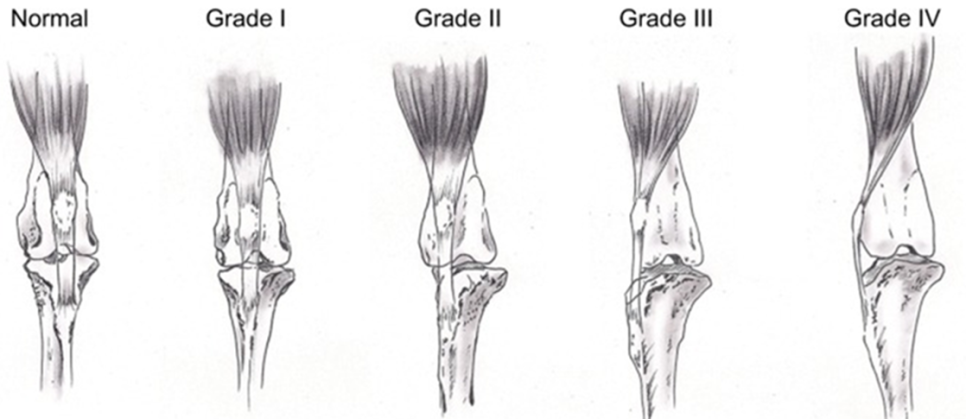

슬개골 탈구는 크게 4단계로 나눌 수 있습니다.

보통 슬개골 탈구 수술을 위해 내원하는 환자들의 경우 3기 이상이 대부분이지만,

1기 혹은 2기라 하더라도 통증을 나타내거나 진행 속도고 빠른 경우에는 수술적 교정이 필요합니다.